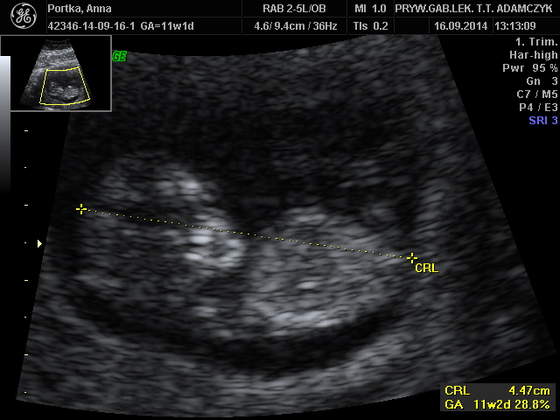

PORTKA_1.jpg

oto i moje śliczne maleństwo :**

28,7 KB · Wyświetleń: 183